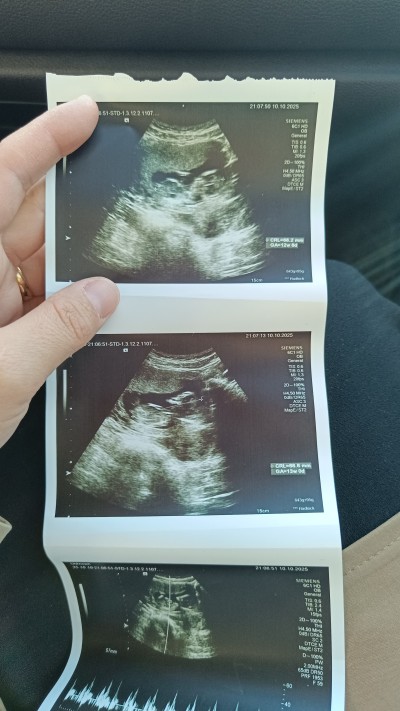

13 haftalık hamileyim bana da demedi , insan merakta ediyor

Maalesef demedi şuan 14 haftalık oldum, bakalım gelecek kontrolde artık